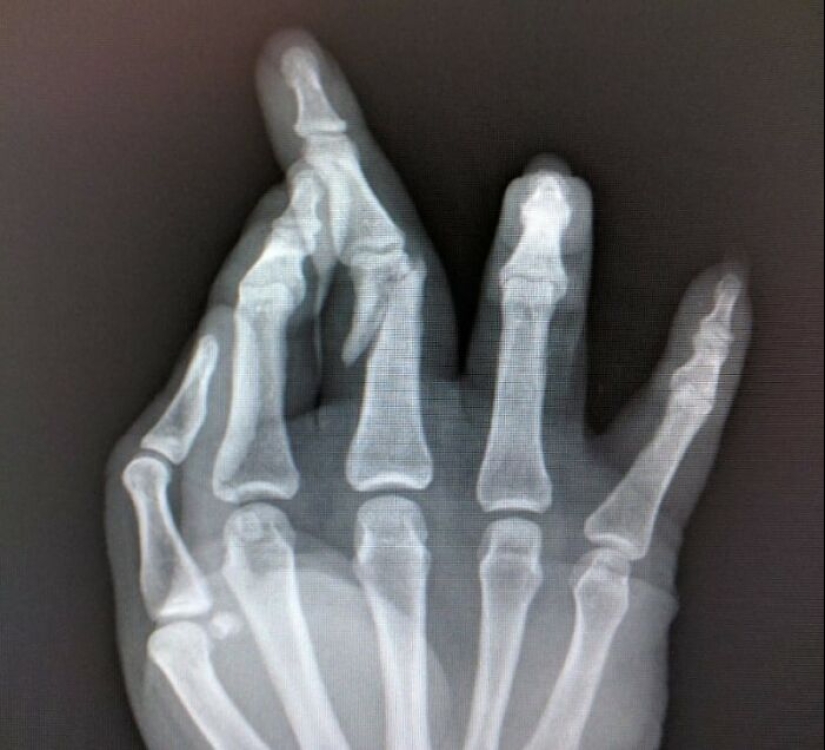

I'm a wheelchair user and I once tried to show off in a club by getting up this pretty big step to dance on the raised area. Fell backwards and punched the floor when I landed, breaking my hand (though I didn't realise it until the next day)

About 2 minutes later my partner tried to do the same thing and got a nearly identical injury

Who could have predicted that taking a GIANT step (like 4x the size of a curb) with no run-up, on a slippy dance floor with slippy wheels, and nothing to grab onto, could have POSSIBLY gone wrong.... not us?